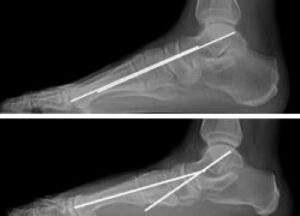

To confirm the diagnosis and assess the severity of the condition, your doctor may recommend imaging tests, including: X-rays: X-rays provide detailed images of bones and are essential for detecting issues like arthritis or changes in bone alignment that contribute to pain and deformities. For flatfoot, weightbearing X-rays (taken while standing) are particularly helpful, as they reveal deformities more accurately than non-weightbearing images. If surgery is being considered, X-rays also assist in measuring deformities and planning the most appropriate surgical approach.

(Top) An X-ray of a normal foot. Note that a line through the center of the ankle bone (talus) and a line through the rest of the foot are parallel, indicating a normal arch. (Bottom) In this X-ray the lines diverge, which is consistent with flatfoot deformity.